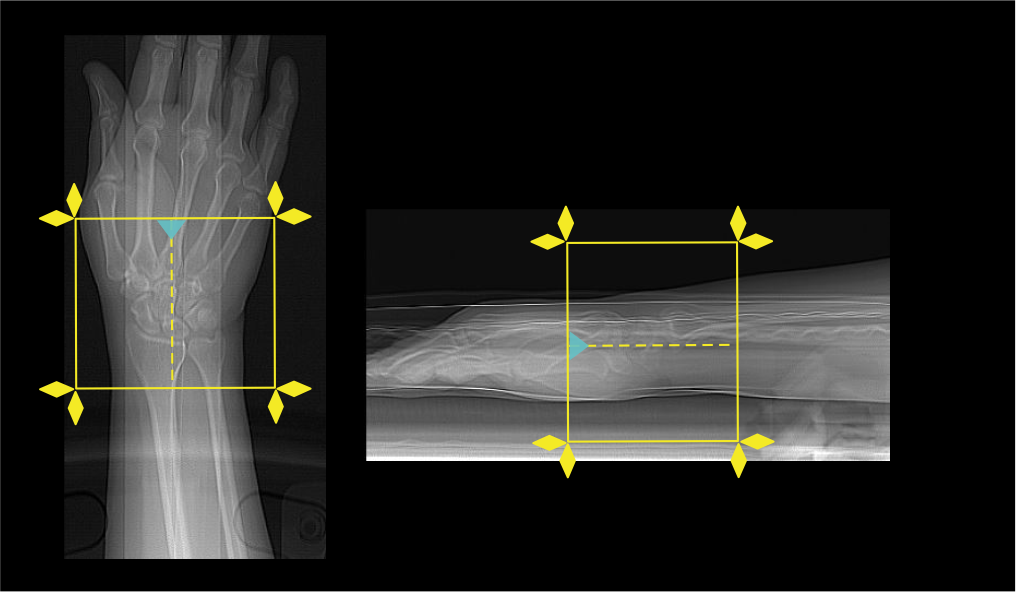

Scan planning

- Plan the scan slab to cover from the radioulnar joint to base of the metacarpals.

- Reduce the field of view (FOV) as appropriate to include wrist joint.

Explanation: small FOV increases geometric resolution.